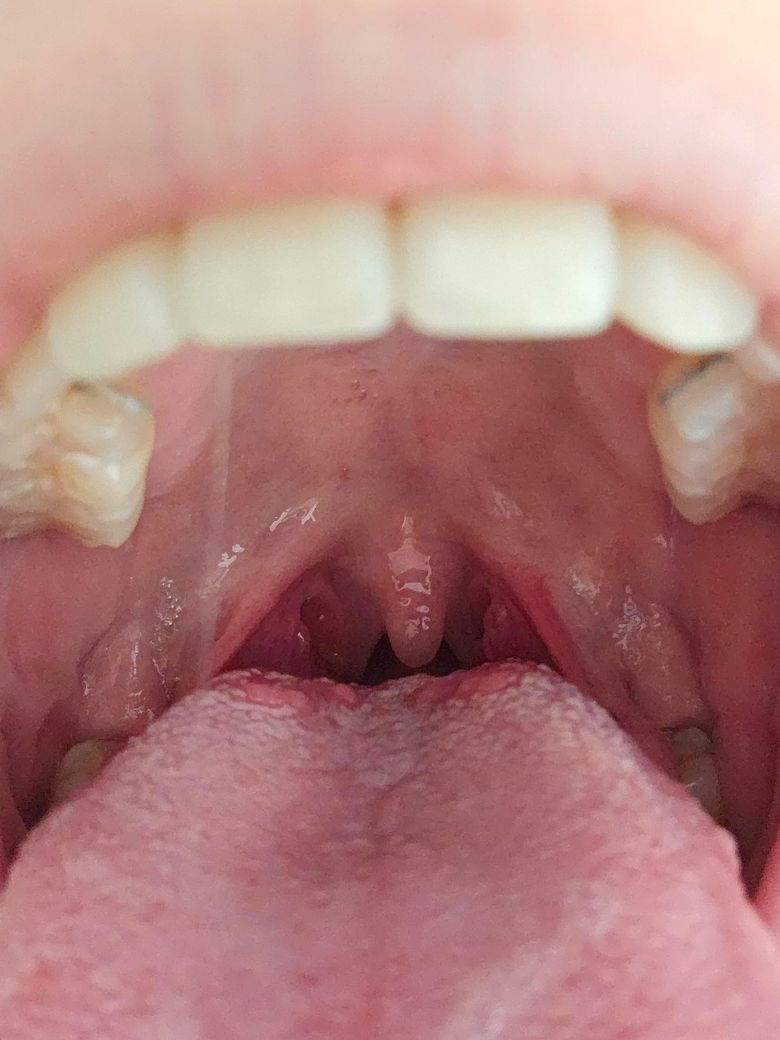

• 1번 째 사진

• 농양이 생긴 이후에 일종의 후유증 마냥 증상이 일시적으로 발생하였을 가능성이 있어 보입니다. 일단 올리신 사진을 통해서 보았을 때에는 농양이나 심한 염증 소견 등이 따로 있어 보이지 않습니다. 일단은 약물을 복용하면서 조금 더 경과를 지켜보아도 무방할 것으로 사료되긴 합니다만, 상태에 대한 자세한 재평가를 희망한다면 치료를 받으셨던 병원에서 한 번 더 검진을 받아보시는 것이 도움이 될 수도 있겠습니다.